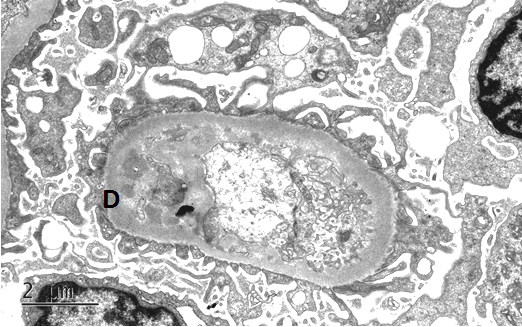

紫癜性肾炎的病理改变

光镜病理分型-ISKDC